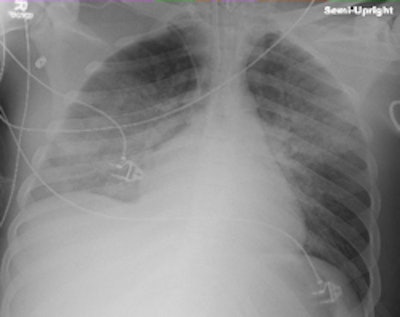

![]() |

| Routine daily radiographs of ventilated patients in the ICU can often be avoided without affecting clinical outcomes. Image courtesy of Dr. Yuji Oba. |